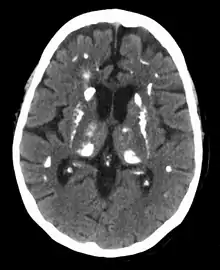

Hyperparathyroidism can cause hyperchloremia and increase renal bicarbonate loss, which may result in a normal anion gap metabolic acidosis.[7] ALP level can be elevated due to bone turnover. Additionally further tests can be completed to rule out other causes and complications of hyperparathyroidism including a 24-hour urinary calcium for familial hypocalciuric hypercalcemia, DEXA scan to evaluate for osteoporosis, osteopenia, or fragility fractures, and genetic testing.[36][37][38][39] Additionally a CT scan without contrast or renal ultrasound can be done to assess for nephrolithiasis and/or nephrocalcinosis if there is concern for it.[39]